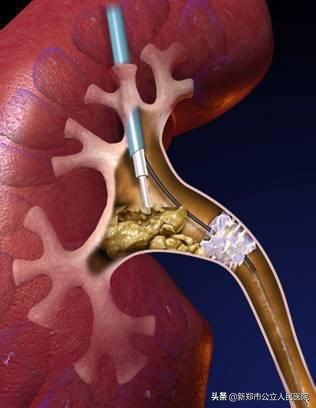

不同于传统硬性输尿管镜,输尿管软镜是一种头部可以随意弯曲的软性内镜。

它能通过弯曲的输尿管到达肾内,并到达传统硬性输尿管镜无法到达的肾脏内上、中、下盏区域,在不造成任何体表损伤的情况下,输尿管软镜可以通过人体自然腔道完成肾脏结石的碎石、清石手术,是先进的微创手术。

泌尿团队结合患者病情,决定为其行输尿管软镜下肾盂钬激光碎石术。在做好充分术前准备后,协同麻醉医师、手术室护士在全麻下为患者实施手术。术后肾盂内的结石被碎成米粒般大小的一堆,从输尿管里尽数取出,手术过程顺利,术中无出血。